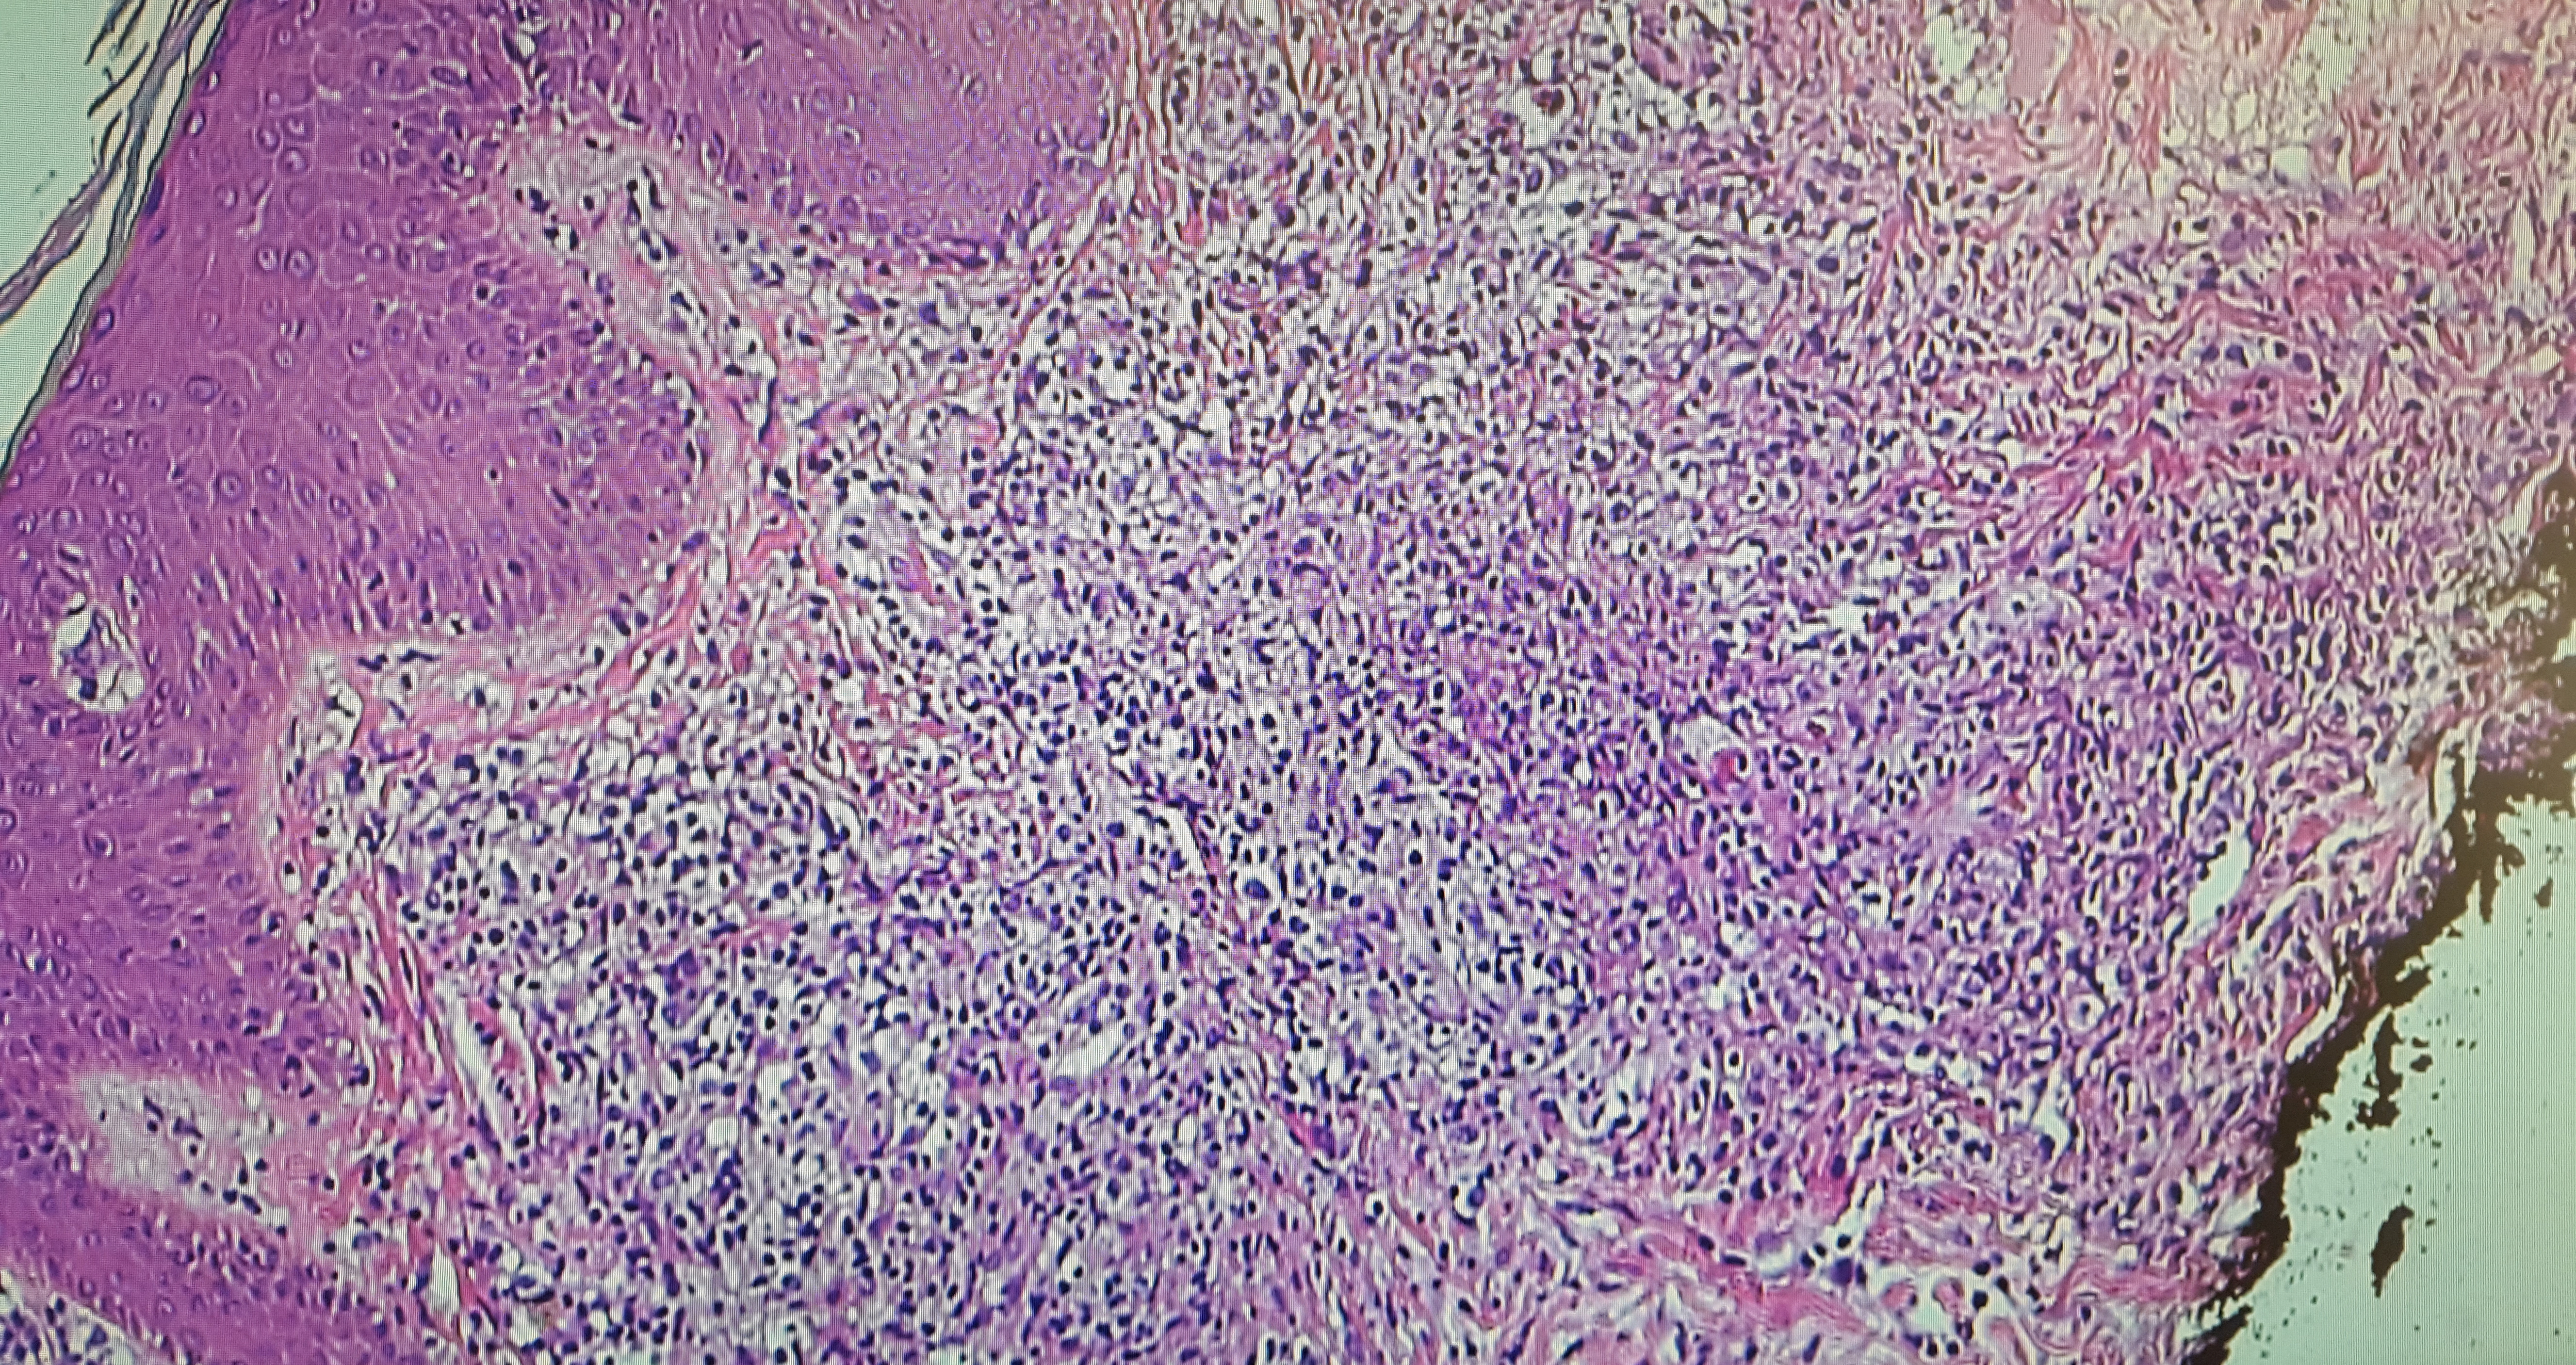

The final pathology report of the skin biopsy showed positive immunohistochemical staining for CD2/3-positive T cells with predominantly infiltrating CD4+ cells. CD20+ cells predominated around blood vessels, with evidence of Epstein-Barr virus (EBV)–positive cells infiltrating the tissue and blood vessels (Figures 3 and 4). Immunohistochemical staining was negative for CD56, ruling out the initial diagnosis of NK/T-cell lymphoma.

Figure 3. Hematoxylin-eosin stain showing a superficial and deep diffuse inflammatory infiltrate composed of polymorphous lymphocytes.